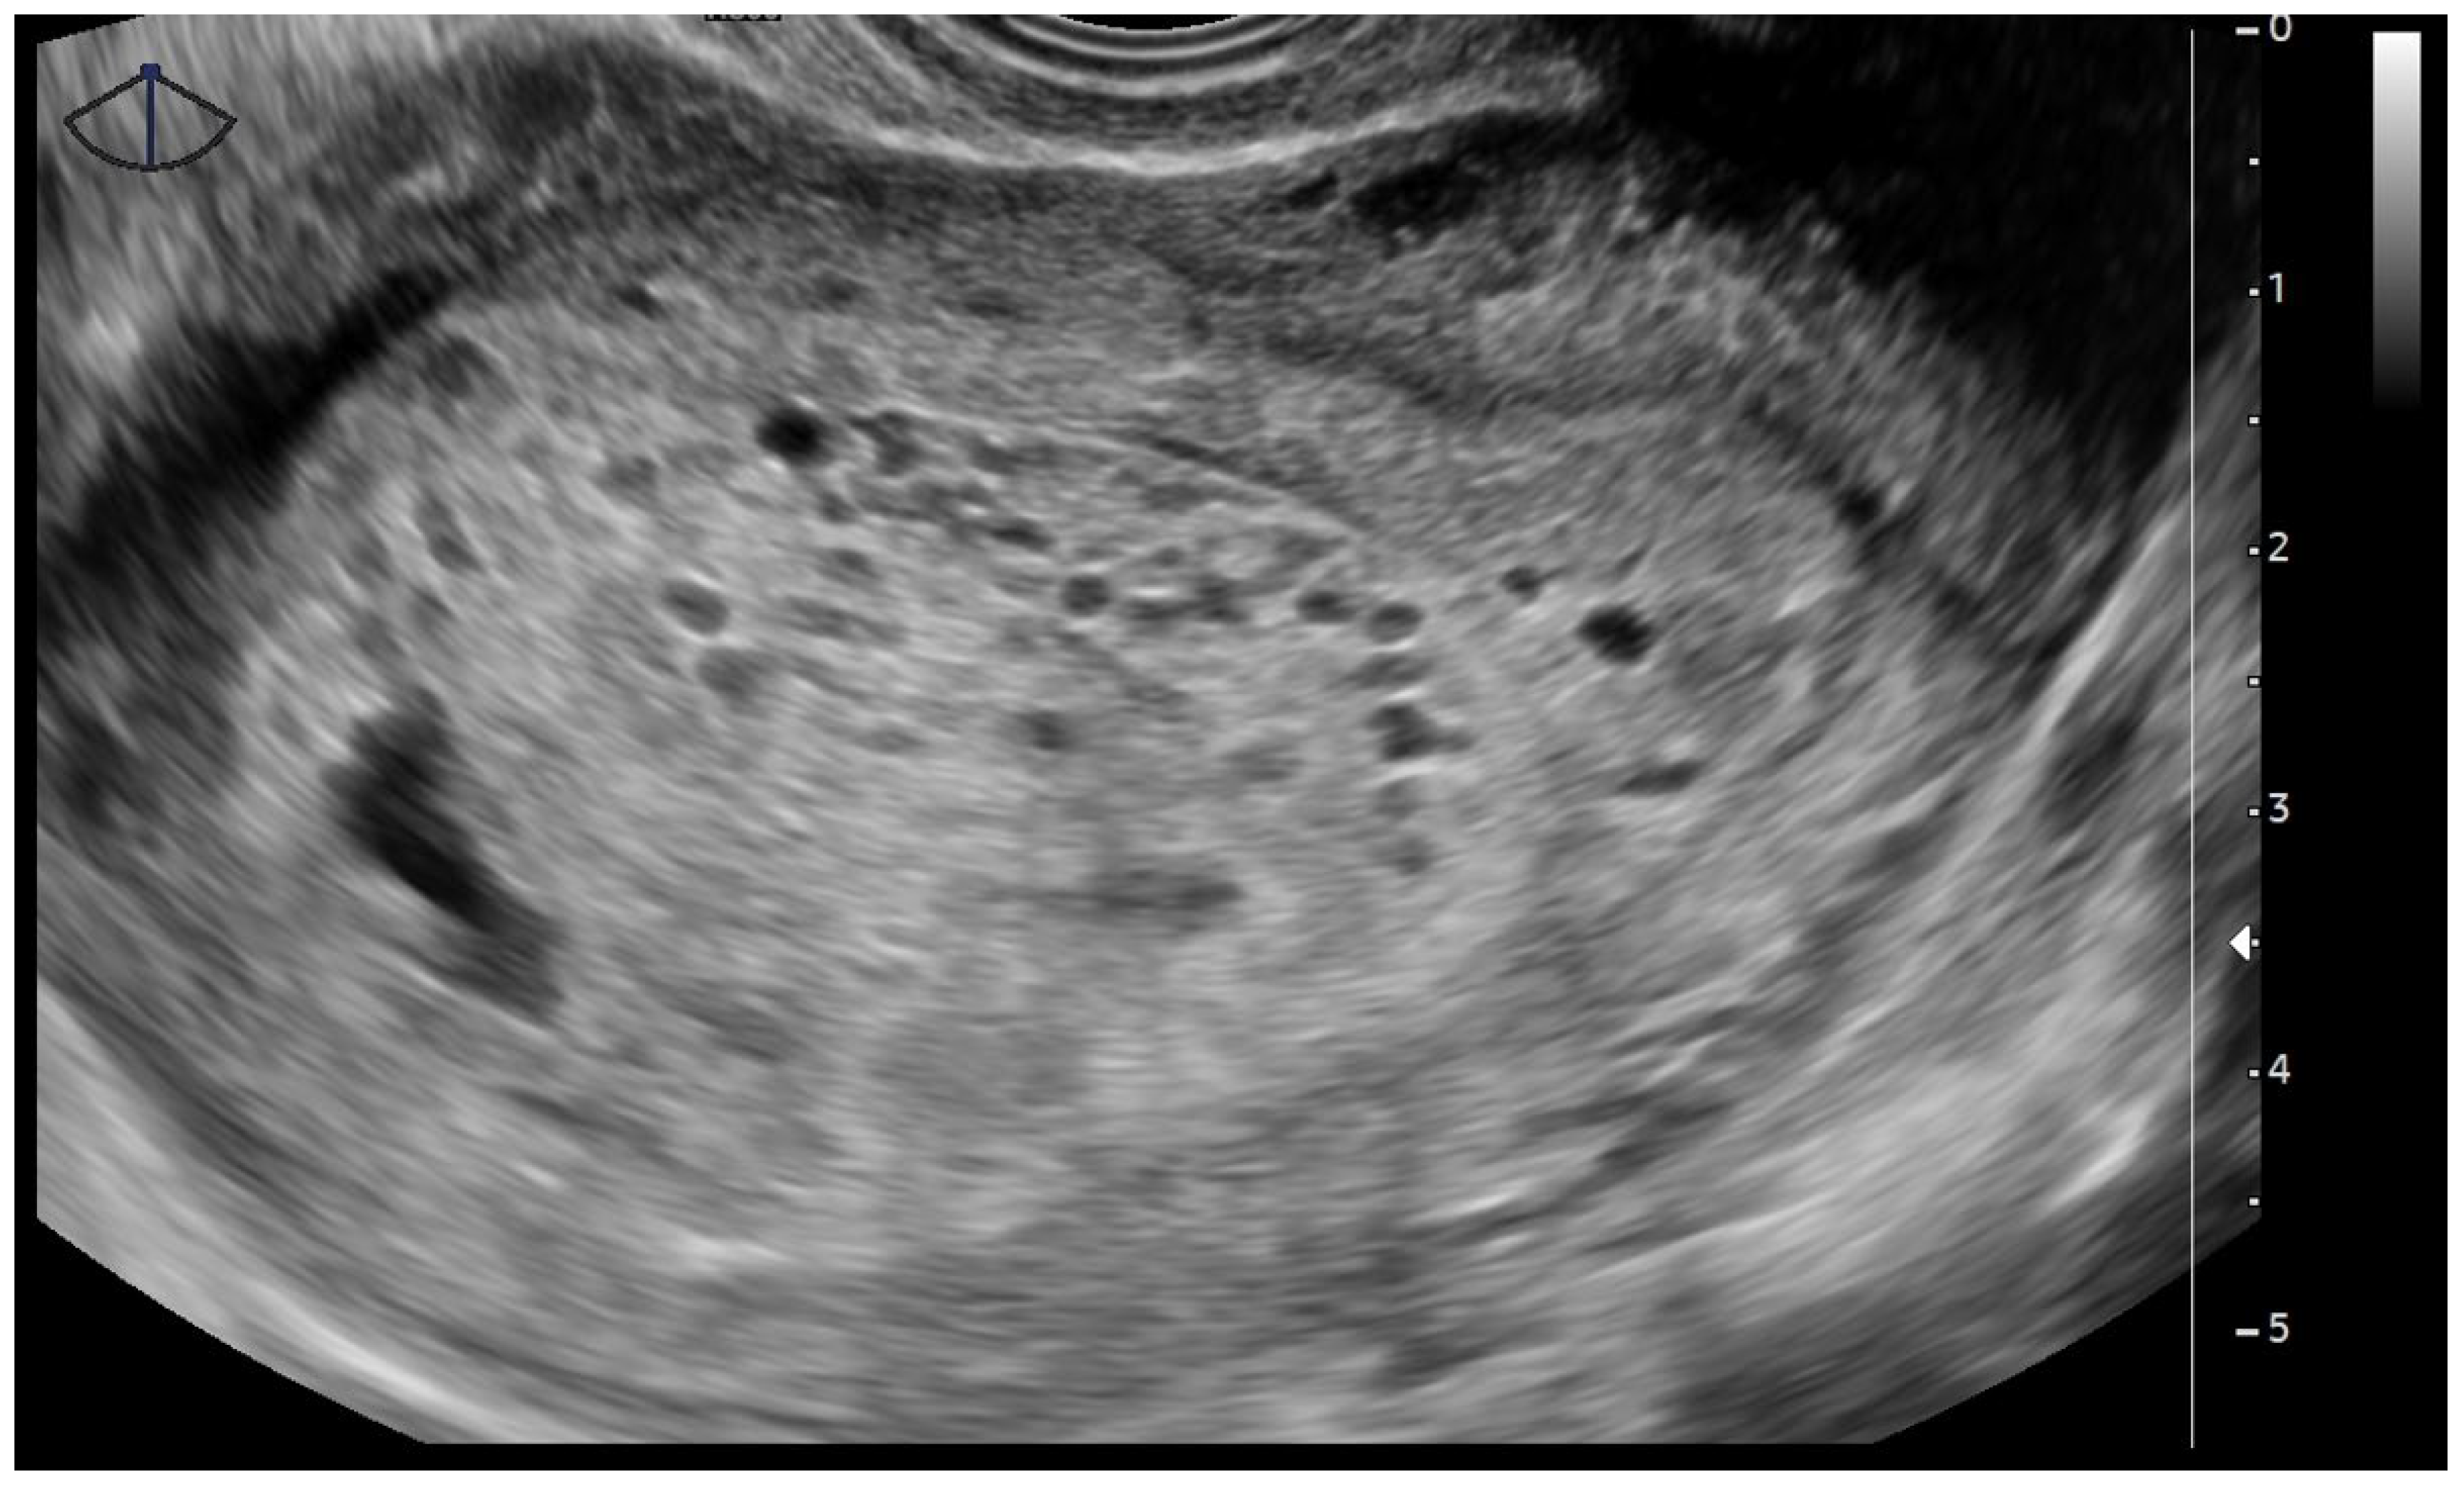

2.3. Pelvic Transvaginal Ultrasound

- Newhouse, I.; Spacey, A.; Scragg, B.; Szczepura, K. The diagnostic value and accuracy of ultrasound in diagnosing hydatidiform mole: A systematic review and meta-analysis of the literature. Radiography 2022, 28, 897–905. [Google Scholar] [CrossRef] [PubMed]

- Savage, J.L.; Maturen, K.E.; Mowers, E.L.; Pasque, K.B.; Wasnik, A.P.; Dalton, V.K.; Bell, J.D. Sonographic diagnosis of partial versus complete molar pregnancy: A reappraisal. J. Clin. Ultrasound 2017, 45, 72–78. [Google Scholar] [CrossRef] [PubMed]

- Sebire, N.J.; Rees, H.; Paradinas, F.; Seckl, M.; Newlands, E. The diagnostic implications of routine ultrasound examination in histologically confirmed early molar pregnancies. Ultrasound Obstet. Gynecol. 2001, 18, 662–665. [Google Scholar] [CrossRef]

- Tang, Y.; Zhu, C.; Zhu, C.; Liang, F.; Lee, A.; Yao, X.; Chen, Q. The impact of pre-evacuation ultrasound examination in histologically confirmed hydatidiform mole in missed abortion. BMC Womens Health 2020, 20, 196. [Google Scholar] [CrossRef]